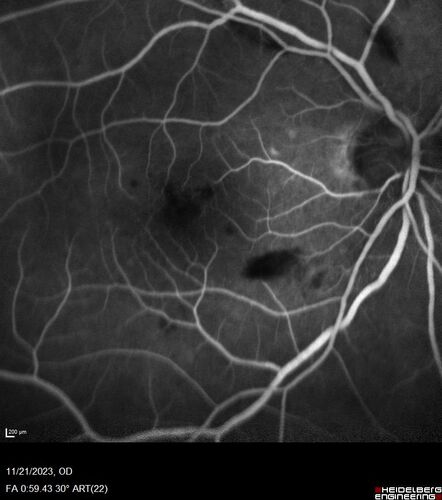

Roth Spot and Endocarditis

70 year old female - flu like symptoms with roth spot who was diagnosed by echo with endocarditis